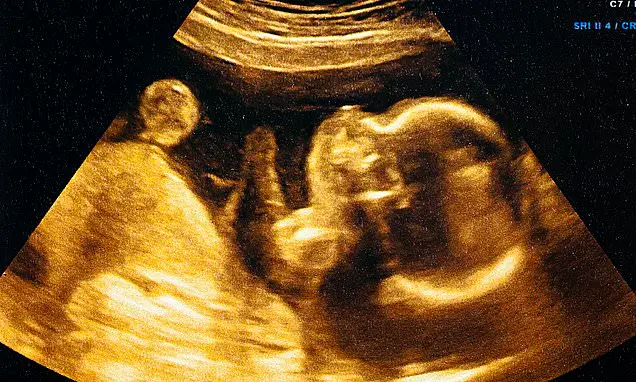

Artificial intelligence applied to ultrasound scans can predict a baby's delivery date with high accuracy. The AI model, developed by Ultrasound AI, analyses ultrasound images to estimate the time until delivery. Testing has shown the AI's accuracy improves with retraining, achieving an accuracy measure of 0.95 for term births.

The AI was trained using over two million ultrasound images from women who delivered at the University of Kentucky. The AI's performance remains consistent across all trimesters and patient demographics. This technology could be especially useful in areas where access to specialist care is limited, enabling early risk identification.